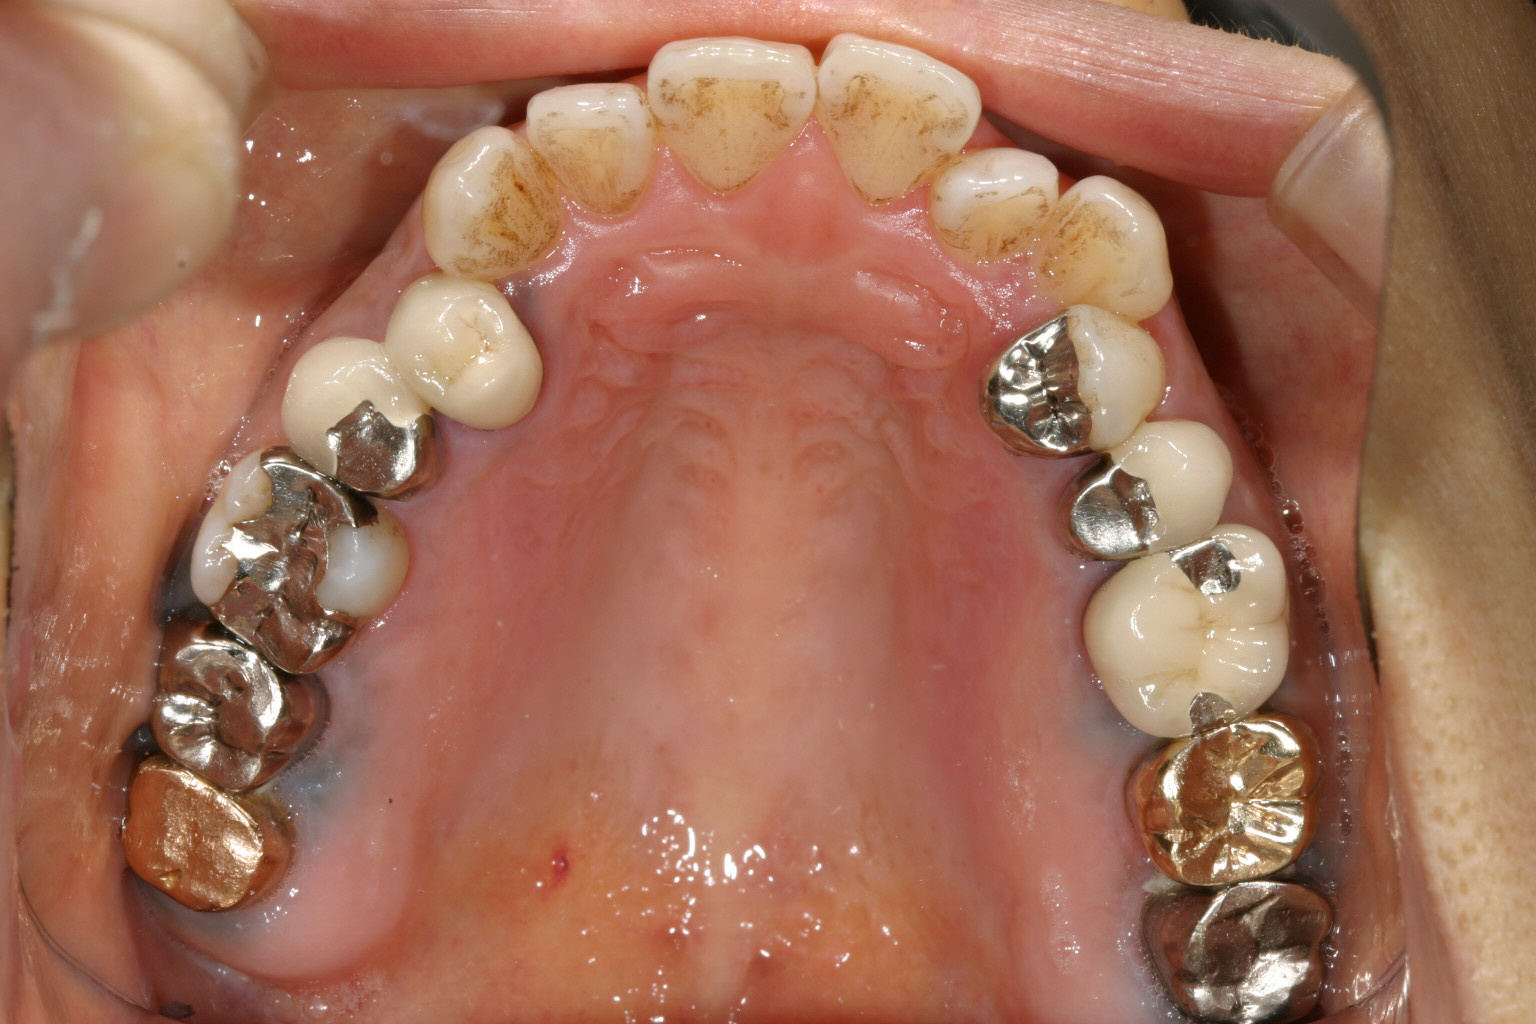

歯の乱れは大した事無いのですが補綴物が多くて治療は大変です。

下顎も補綴物が多く又前歯部にガタガタが見受けられます。